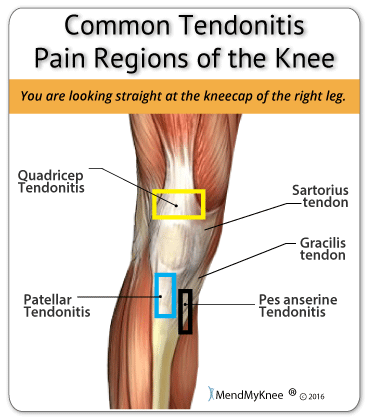

Where or Where Has My Patella Gone Direct Orthopedic Care 2024, Patella Kneecap Anatomy and Function 2024, Patellofemoral Pain Syndrome OrthoInfo AAOS 2024, The Patella Surface Anatomy Functions Dislocation 2024, Patella Wikipedia 2024, Patellar Fractures Broken Kneecap OrthoInfo AAOS 2024, Patellofemoral Joint Structure Function Conditions 2024, Patellofemoral Joint Physiopedia 2024, Patellar region Flashcards Quizlet 2024, Patella Injury Treatments Knee Surgeons Consultants Yorkshire 2024, Patella Anatomy function and clinical aspects Kenhub 2024, Patellar Tendonitis Jumper s Knee Johns Hopkins Medicine 2024, ITB vs Patellofemoral Pain Syndrome Symptoms Knee Pain In Runners 2024, Patellofemoral Pain Syndrome OrthoInfo AAOS 2024, Patella Anatomy function and clinical aspects Kenhub 2024, Patellar Tendonitis Jumpers Knee Symptoms Diagnosis Treatment 2024, Patellofemoral Pain Syndrome Rural Physio at Your Doorstep 2024, Patellar tendinitis Symptoms causes Mayo Clinic 2024, Patella Femoral Syndrome Montgomery Massage Therapy 2024, Jumper s Knee Symptoms in Kids Jumper s Knee Treatment 2024, Anatomy of Patella Bone and Spine 2024, Patellar Tendonitis Jumper s Knee Symptoms Causes Mount 2024, Anatomy Gruppo Bioimpianti 2024, Patellofemoral Pain Syndrome 2024, Patella Tendinopathy also known as Jumper s Knee Complete Physio 2024, Patellofemoral Pain Syndrome PFPS Symptoms Treatment 2024, Patellar Tendonitis 2024, Patellofemoral Joint Physiopedia 2024, How to avoid Runner s Knee . Forty two percent of all overuse 2024, Osgood Schlatter Disease Knee Pain OrthoInfo AAOS 2024, Tendinitis in the Knee 2024, Patella Kneecap Definition Location Anatomy Diagram 2024, Patellar Tendinopathy Rural Physio at Your Doorstep Physio Direct 2024, Knee Pain Location Chart SPORT Orthopedics Dallas and Frisco 2024, 10 Common Knee Injuries Diseases 2024.

Where or Where Has My Patella Gone Direct Orthopedic Care 2024, Patella Kneecap Anatomy and Function 2024, Patellofemoral Pain Syndrome OrthoInfo AAOS 2024, The Patella Surface Anatomy Functions Dislocation 2024, Patella Wikipedia 2024, Patellar Fractures Broken Kneecap OrthoInfo AAOS 2024, Patellofemoral Joint Structure Function Conditions 2024, Patellofemoral Joint Physiopedia 2024, Patellar region Flashcards Quizlet 2024, Patella Injury Treatments Knee Surgeons Consultants Yorkshire 2024, Patella Anatomy function and clinical aspects Kenhub 2024, Patellar Tendonitis Jumper s Knee Johns Hopkins Medicine 2024, ITB vs Patellofemoral Pain Syndrome Symptoms Knee Pain In Runners 2024, Patellofemoral Pain Syndrome OrthoInfo AAOS 2024, Patella Anatomy function and clinical aspects Kenhub 2024, Patellar Tendonitis Jumpers Knee Symptoms Diagnosis Treatment 2024, Patellofemoral Pain Syndrome Rural Physio at Your Doorstep 2024, Patellar tendinitis Symptoms causes Mayo Clinic 2024, Patella Femoral Syndrome Montgomery Massage Therapy 2024, Jumper s Knee Symptoms in Kids Jumper s Knee Treatment 2024, Anatomy of Patella Bone and Spine 2024, Patellar Tendonitis Jumper s Knee Symptoms Causes Mount 2024, Anatomy Gruppo Bioimpianti 2024, Patellofemoral Pain Syndrome 2024, Patella Tendinopathy also known as Jumper s Knee Complete Physio 2024, Patellofemoral Pain Syndrome PFPS Symptoms Treatment 2024, Patellar Tendonitis 2024, Patellofemoral Joint Physiopedia 2024, How to avoid Runner s Knee . Forty two percent of all overuse 2024, Osgood Schlatter Disease Knee Pain OrthoInfo AAOS 2024, Tendinitis in the Knee 2024, Patella Kneecap Definition Location Anatomy Diagram 2024, Patellar Tendinopathy Rural Physio at Your Doorstep Physio Direct 2024, Knee Pain Location Chart SPORT Orthopedics Dallas and Frisco 2024, 10 Common Knee Injuries Diseases 2024.